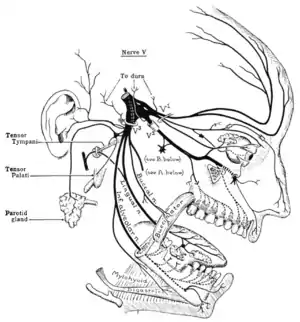

Schematic illustration of the trigeminal nerve and the organs (or structures) it supplies | |

In neuroanatomy, the trigeminal nerve (lit. triplet nerve), also known as the fifth cranial nerve, cranial nerve V, or simply CN V, is a cranial nerve responsible for sensation in the face and motor functions such as biting and chewing; it is the most complex of the cranial nerves. Its name (trigeminal, from Latin tri- 'three', and -geminus 'twin'[1]) derives from each of the two nerves (one on each side of the pons) having three major branches: the ophthalmic nerve (V1), the maxillary nerve (V2), and the mandibular nerve (V3). The ophthalmic and maxillary nerves are purely sensory, whereas the mandibular nerve supplies motor as well as sensory (or "cutaneous") functions.[2] Adding to the complexity of this nerve is that autonomic nerve fibers as well as special sensory fibers (taste) are contained within it.

Origin

From the trigeminal ganglion, a single, large sensory root (radix sensoria s. portio major) enters the brainstem at the level of the pons. Immediately adjacent to the sensory root, a smaller motor root (radix motoria s. portio minor) emerges from the pons[3] slightly rostrally and medially to the sensory root.[4]

Motor fibers pass through the trigeminal ganglion without synapsing on their way to peripheral muscles, their cell bodies being located in the nucleus of the fifth nerve, deep within the pons.

Trigeminal ganglion

The three major branches of the trigeminal nerve—the ophthalmic nerve (V1), the maxillary nerve (V2) and the mandibular nerve (V3)—converge on the trigeminal ganglion (also called the semilunar ganglion or gasserian ganglion), located within Meckel's cave and containing the cell bodies of incoming sensory-nerve fibers. The trigeminal ganglion is analogous to the dorsal root ganglia of the spinal cord, which contain the cell bodies of incoming sensory fibers from the rest of the body.

Sensory branches

Muscles

The motor component of the mandibular division (V3) of the trigeminal nerve controls the movement of eight muscles, including the four muscles of mastication: the masseter, the temporal muscle, and the medial and lateral pterygoids. The other four muscles are the tensor veli palatini, the mylohyoid, the anterior belly of the digastric and the tensor tympani.